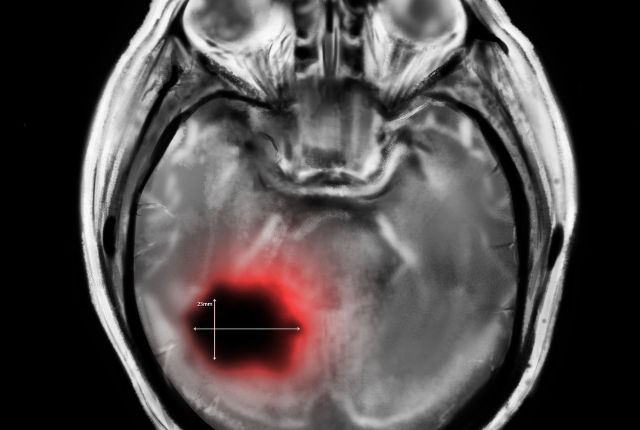

Les astrocytomes sont les tumeurs cérébrales les plus courantes. Certaines sont bénignes comme les astrocytomes pilocytiques, d'autres sont malignes comme les astrocytomes anaplasiques.

Les astrocytomes sont considérés comme les tumeurs cérébrales les plus courantes. Elles concernent plus généralement le système nerveux central. Plus de la moitié des tumeurs cérébrales primitives sont ainsi des astrocytomes. Elles peuvent être bénignes ou malignes. Les astrocytomes sont les tumeurs du cerveau et de la moelle épinière de l'enfant les plus fréquentes. Les astrocytomes appartiennent à type de tumeur au cerveau appelé gliome.

Les glioblastomes (de stade IV) sont la forme la plus dangereuse d'astrocytome. Le glioblastome est le plus fréquent chez les adultes et les personnes âgées.

Les astrocytomes anaplasiques sont des tumeurs gliales rares, malignes, et souvent de grade élevé. Ces tumeurs rentrent dans la catégories des cancers du cerveau comme les glioblastomes. On parle de gliomes malins. L'astrocytome anaplasique touche plus fréquemment les hommes de 40 à 60 ans. Il peut dégénérer en glioblastome qui n'est pas un cancer de très bon pronostic.

Un astrocytome de grade 4 peut être un glioblastome, qui est considéré comme l'astrocytome le plus agressif. Certains scientifiques commencent à remettre en cause ce point en différenciant l'astrocytome qui a une mutation sur une enzyme appelée IDH du glioblastome qui n'a pas cette mutation. Mais, dans les deux cas, ces cancers cérébraux sont connus pour être agressifs.